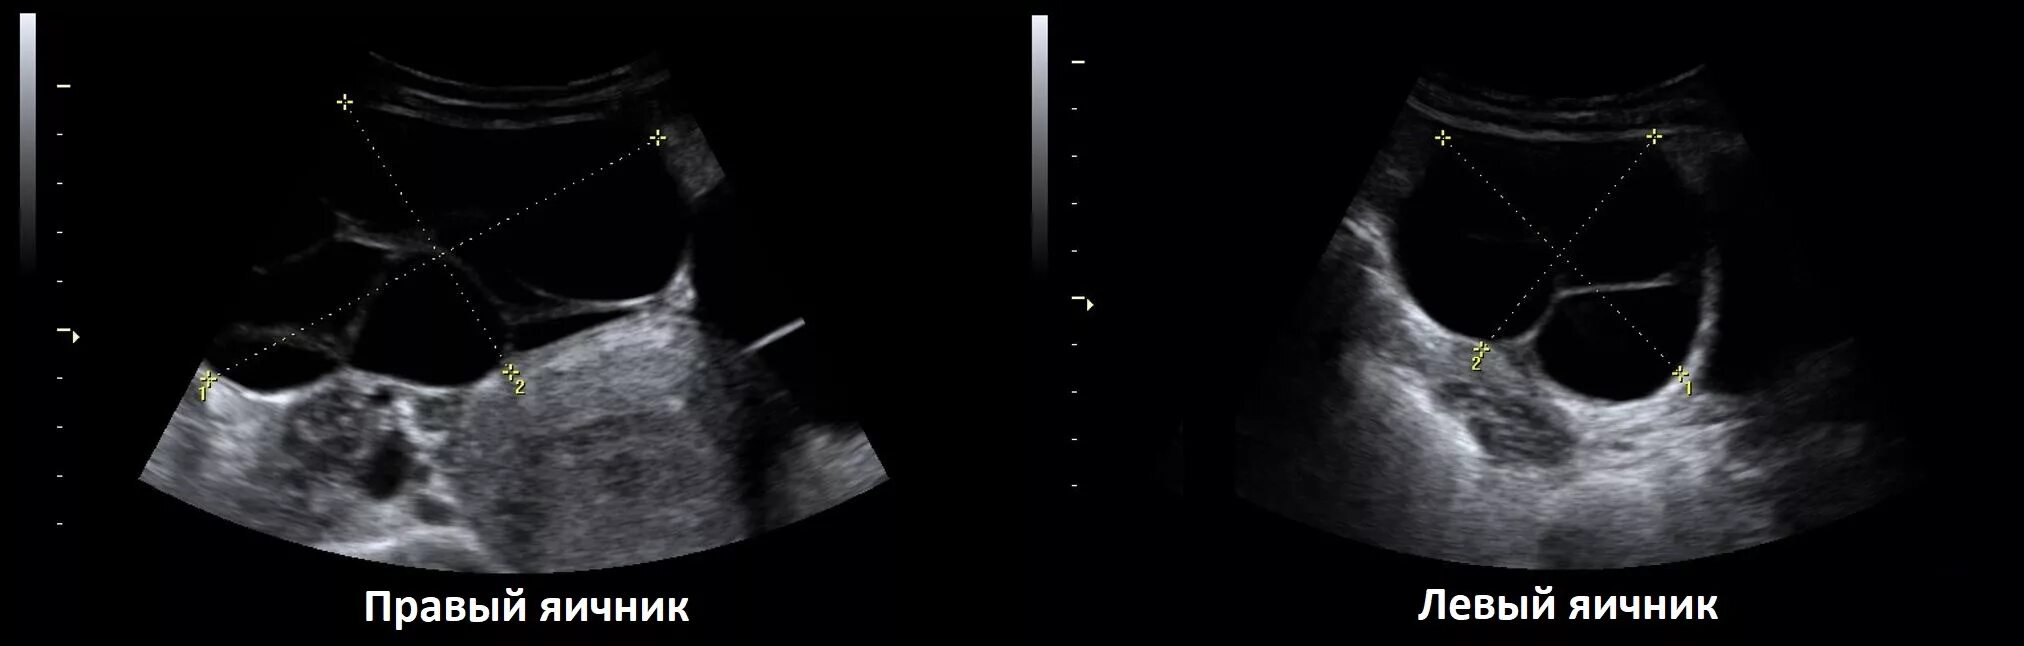

Как выглядит яичник